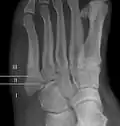

- Proximal diaphysis, typically stress fracture.[12][13]

- Metaphysis: Jones fracture[14]

-Tuberosity: Pseudo-Jones fracture[15] (avulsion fracture).[15]

Normal anatomy:

- Apophysis: Normal at 10 - 16 years.[16]

- Os vesalianum, an accessory bone.[17]

Other proximal fifth metatarsal fractures exist, although they are not as problematic as a Jones fracture. If the fracture enters the intermetatarsal joint, it is a Jones fracture. If, however, it enters the tarsometatarsal joint, then it is likely an avulsion fracture caused by pull from the fibularis brevis tendon. An avulsion fracture at the base of the fifth metatarsal is sometimes called a "dancer's fracture" or a "pseudo Jones fracture", and usually responds readily to non-operative treatment.[18] The X-ray appearance of the developmental "apophysis" in this area may have some resemblance of a fracture, but is not a fracture; it is the secondary ossification center of the metatarsal bone. It is a normal finding that occurs at this site in adolescents.[19] If an injury to that area has occurred, the physician is often able to interpret certain radiographic clues to make the differentiation. An avulsion fracture at this location is typically extra-articular and oriented transversally as compared to the longitudinal orientation of an unfused apophysis.[19]

For several reasons, a Jones fracture may not unite. The diaphyseal bone (zone II), where the fracture occurs, is an area of potentially poor blood supply, existing in a watershed area between two blood supplies. This may compromise healing. In addition, there are various tendons, including the fibularis brevis and fibularis tertius, and two small muscles attached to the bone. These may pull the fracture apart and prevent healing.

Zones I and III have been associated with relatively guaranteed union and this union has taken place with only limited restriction of activity combined with early immobilization. On the other hand, zone II has been associated with either delayed or non-union and, consequently, it has been generally agreed that fractures in this area should be considered for some form of internal immobilization, such as internal screw fixation.

These zones can be identified anatomically and on x-ray adding to the clinical usefulness of this classification.[21] Surgical intervention is not, by itself, a guarantee of cure and has its own complication rate. Other reviews of the literature have concluded that conservative, non-operative, treatment is an acceptable option for the non-athlete.[22]